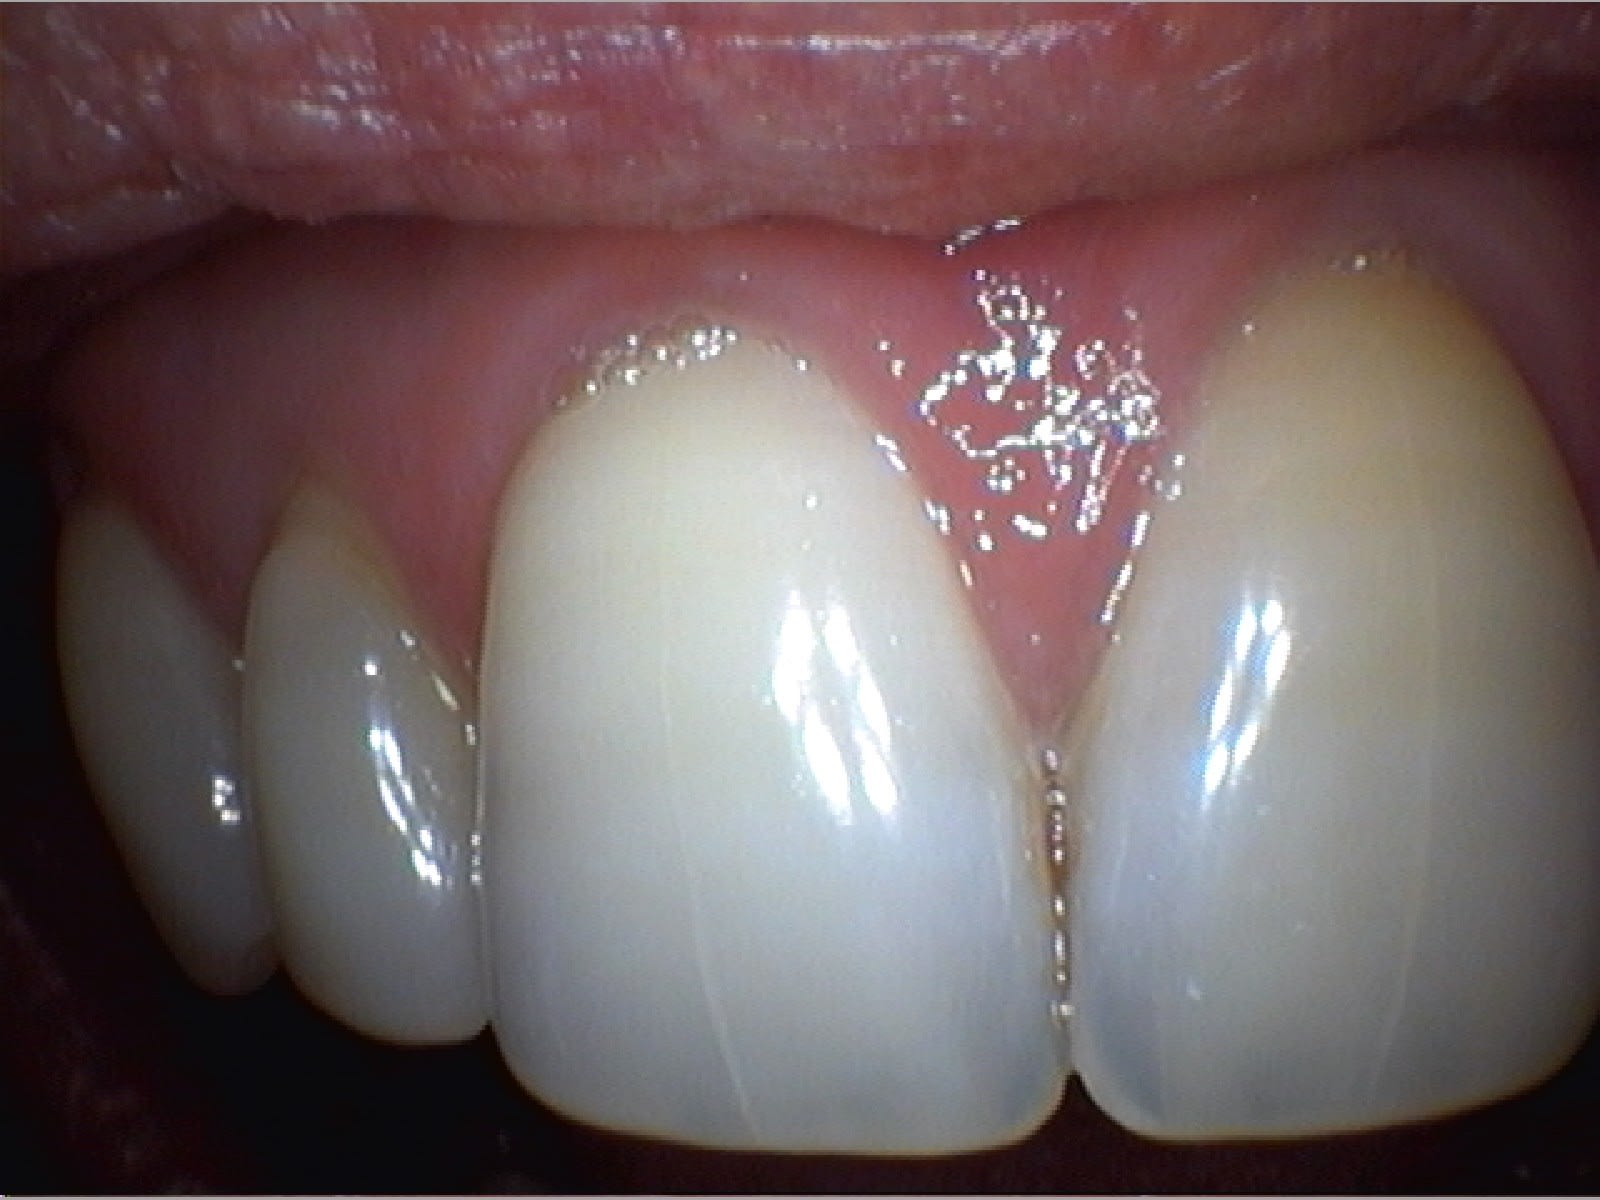

Spécial Gérard !

À la fin de la page 1

On est bien d'accord Pluton, c'est de la merde, mais immédiate en acquisition et très pratique pour caser une CCM !

C'est un peu comme comparer une Rx argentique et une RVG.

J'ai remonter le post pour un copain nonolien qui voulait savoir comment on gère le double mélange à l'Impregum. Simplement pour montrer le berceau gingival sans saignement.